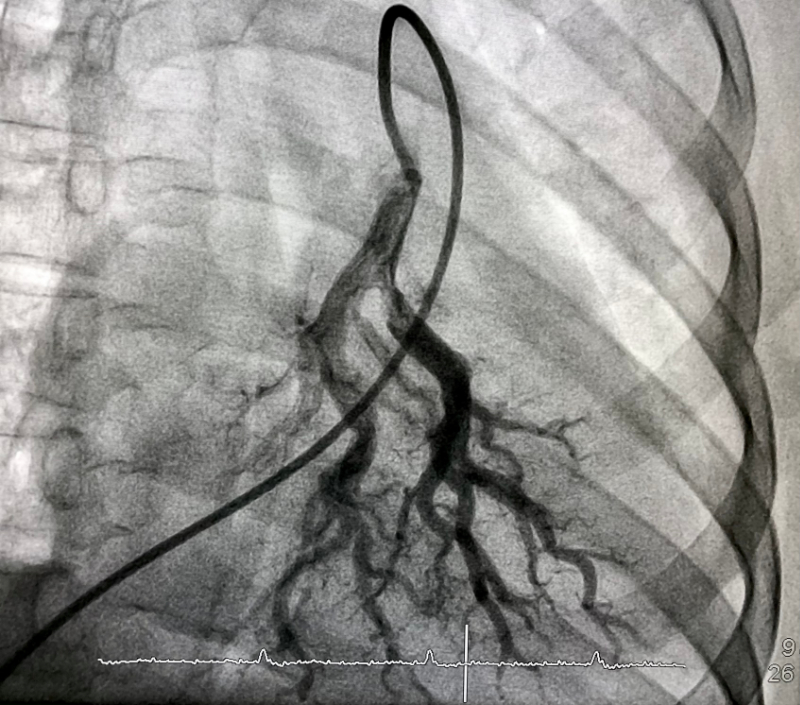

Computed tomography pulmonary angiogram (CPTA): Often, a CPTA is the preferred imaging source when aiming to diagnose PE. It appears to be cost-effective, minimally invasive, and often readily accessible. However, they are usually contraindicated in pregnancy (Moore et al., 2018).

Pulmonary Angiography

CPTA has high sensitivity, and now that the imaging technique has had modifications, the amount of false negatives is low. If a CPTA is positive, often, no further tests are performed, and treatment for PE is initiated (Doğan et al., 2015).

A physical exam was completed, and no murmurs, adventitious breath sounds, or lower extremity edema were noted. An EKG was performed, and sinus tachycardia was evident. Pulmonary angiography was performed and denoted a saddle PE across both pulmonary arteries with evidence of right-sided heart strain.

Based on the symptoms and clinical presentation, the healthcare provider could recognize the severity of the situation. After confirmation of the diagnosis by pulmonary angiography, the healthcare provider also knew the patient would be considered hemodynamically unstable, and immediate action was necessary.